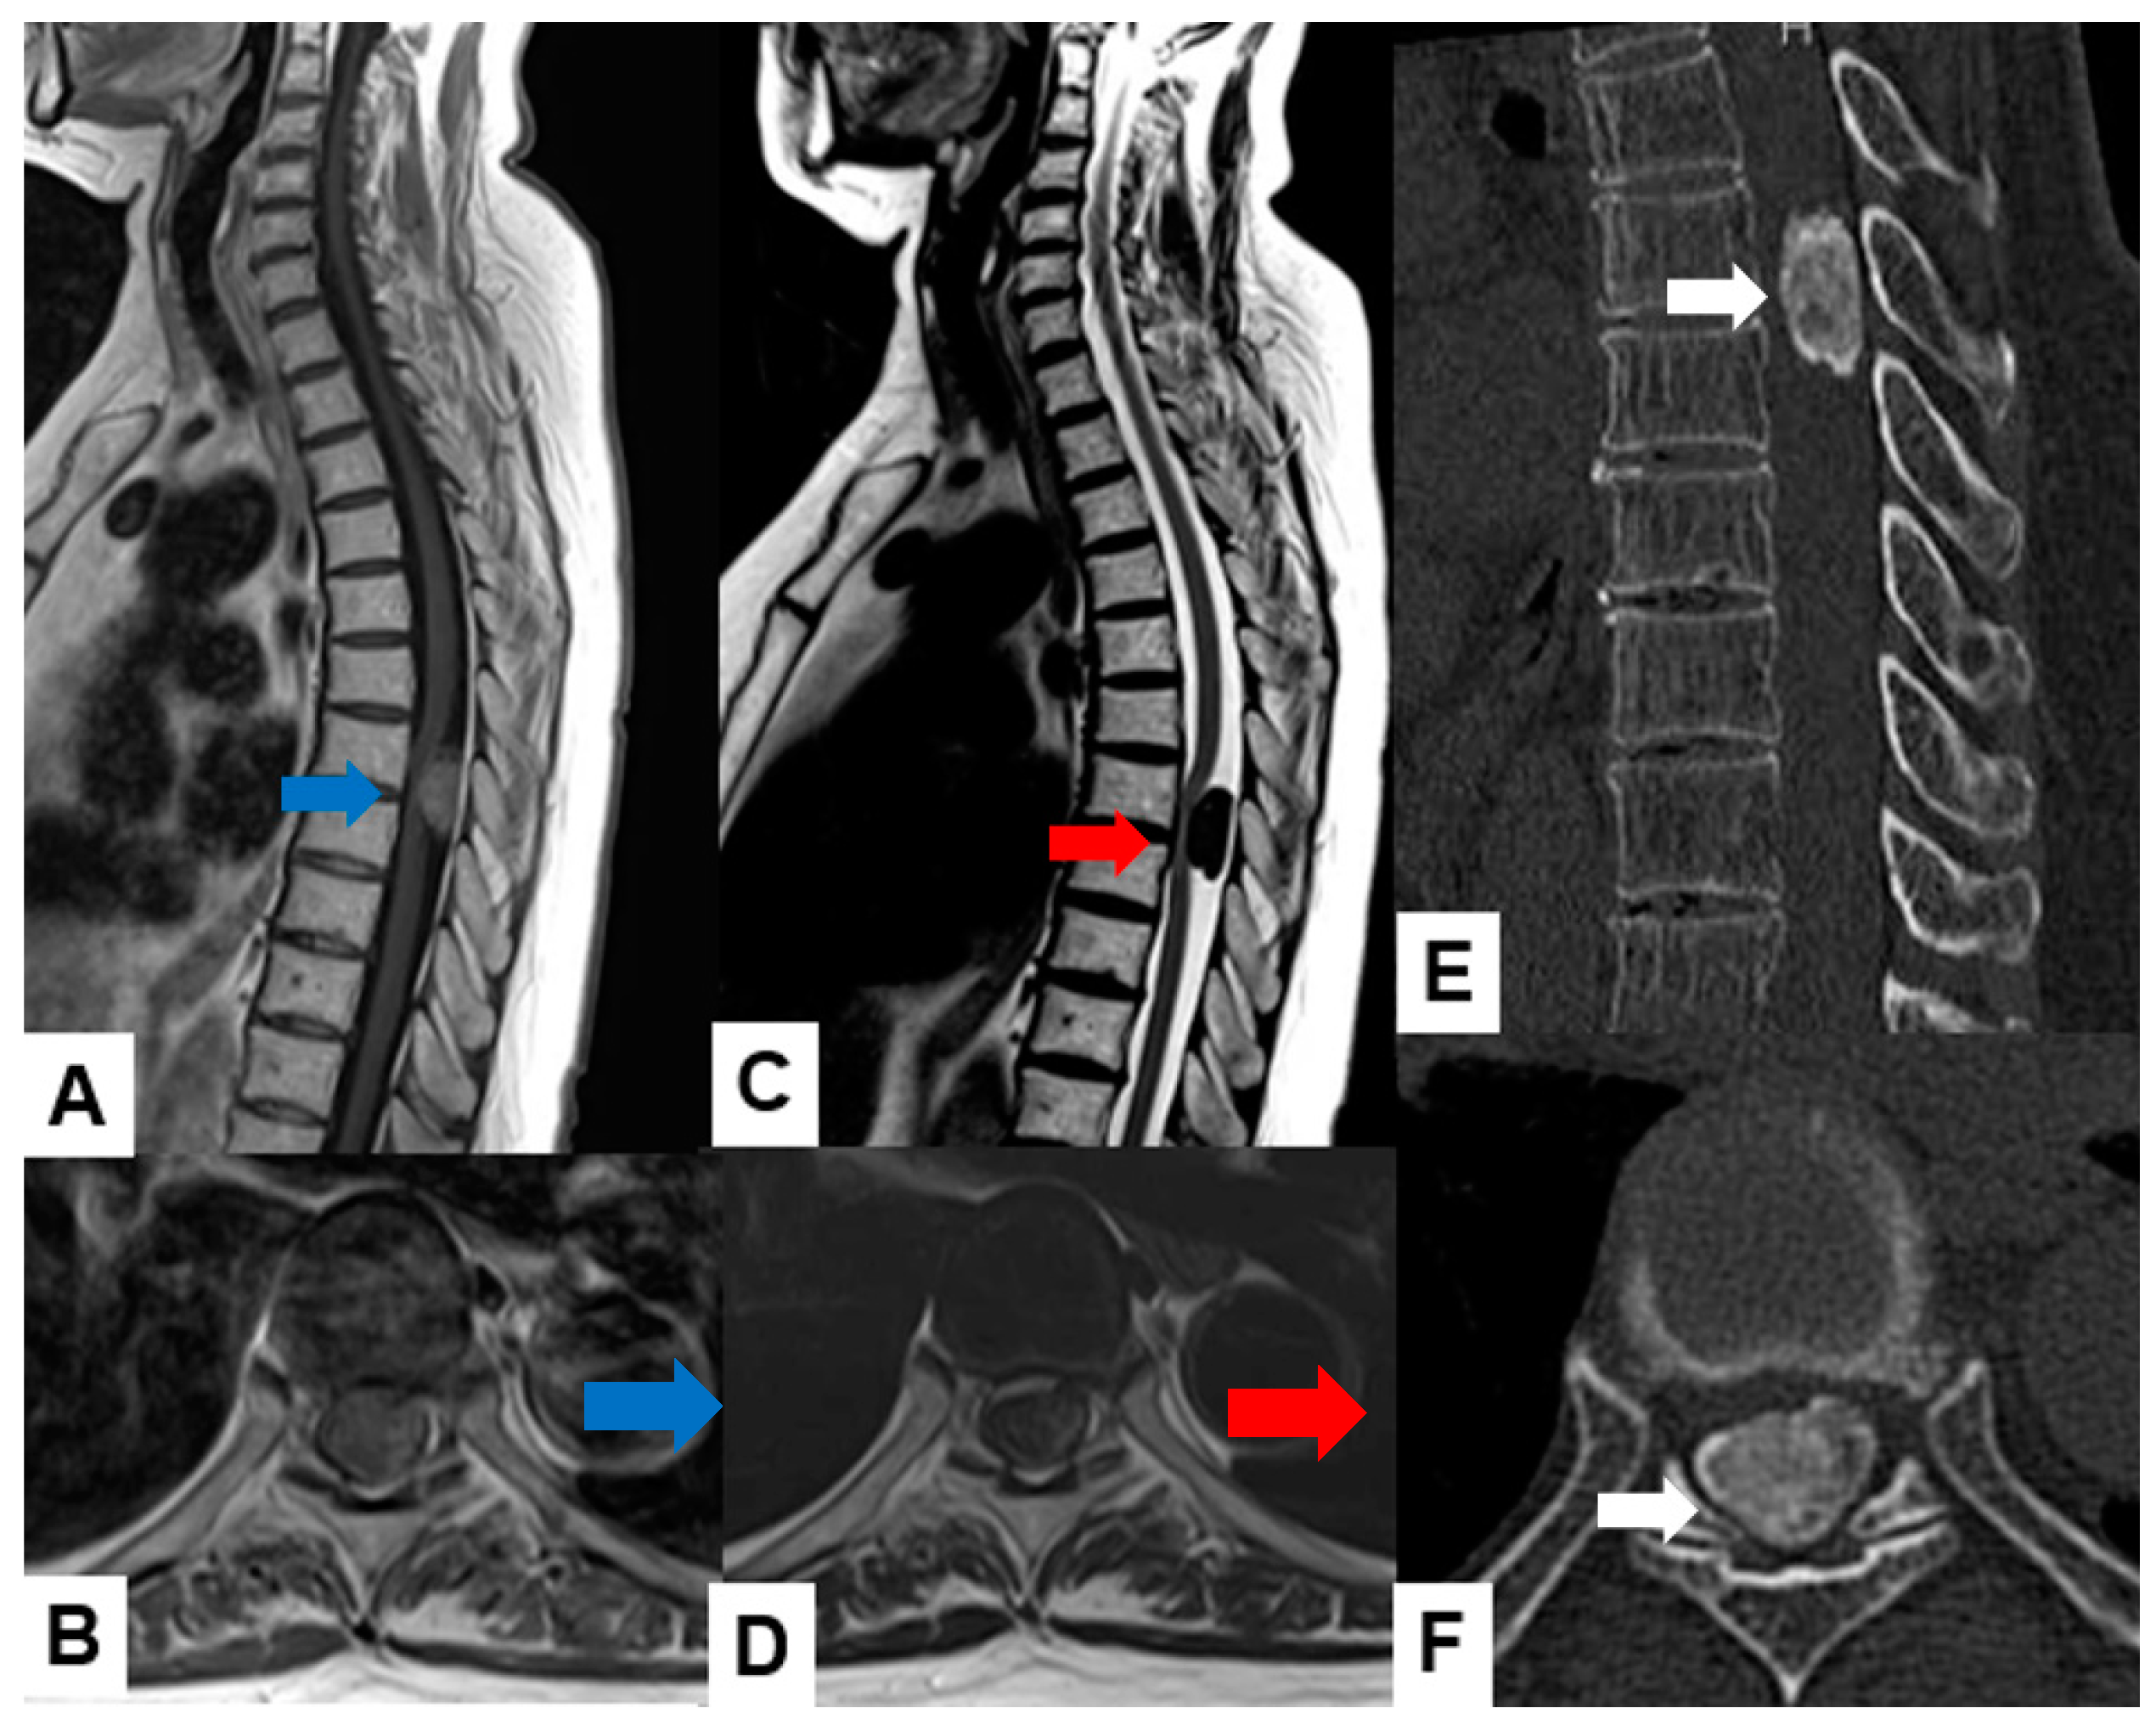

2.1. MRI and CT